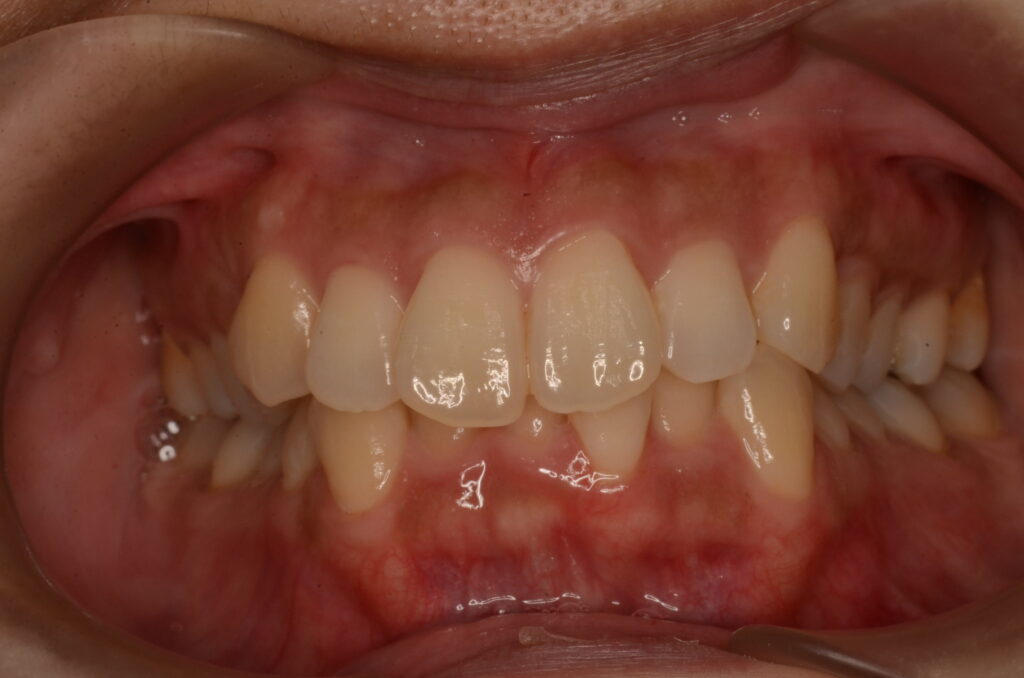

- BEFORE

| 治療内容 | 患者様は、上顎前歯の突出や歯列の叢生(ガタつき)、笑った際に歯ぐきが見えすぎること(ガミースマイル)を主訴に来院されました。 診査の結果、抜歯を行うと歯軸の傾斜や歯列の陥没が懸念されたため、非抜歯でのインビザライン治療を計画しました。 |